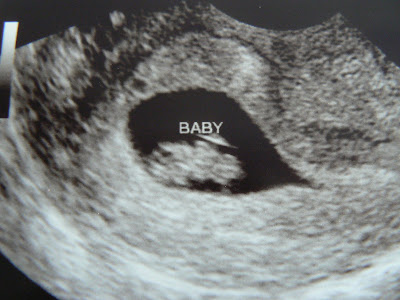

This is my last son at 6 weeks. There is a heart beat

7 weeks

8 weeks

9 weeks

10 weeks

11 weeks